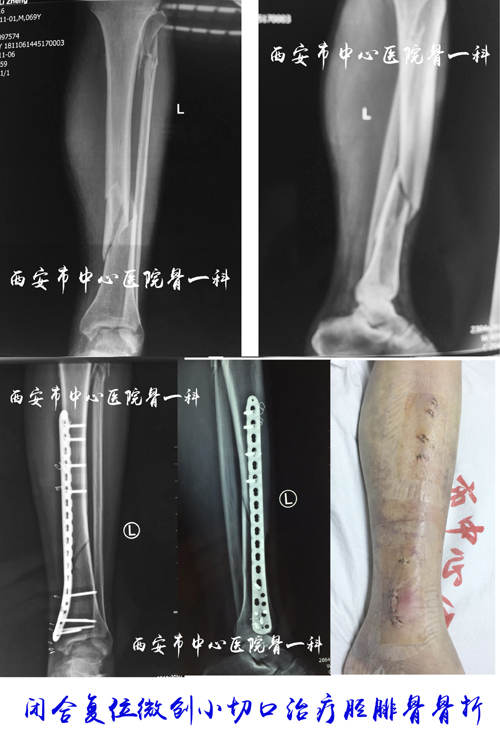

闭合复位经皮螺钉内固定治疗胫腓骨悬崖撒手